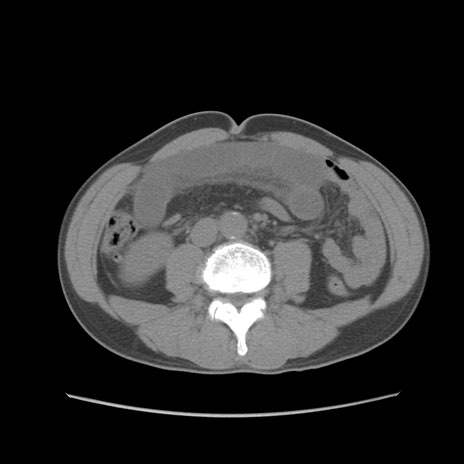

症例56 CT(横断像)

脂肪ウインドウ

冠状断像